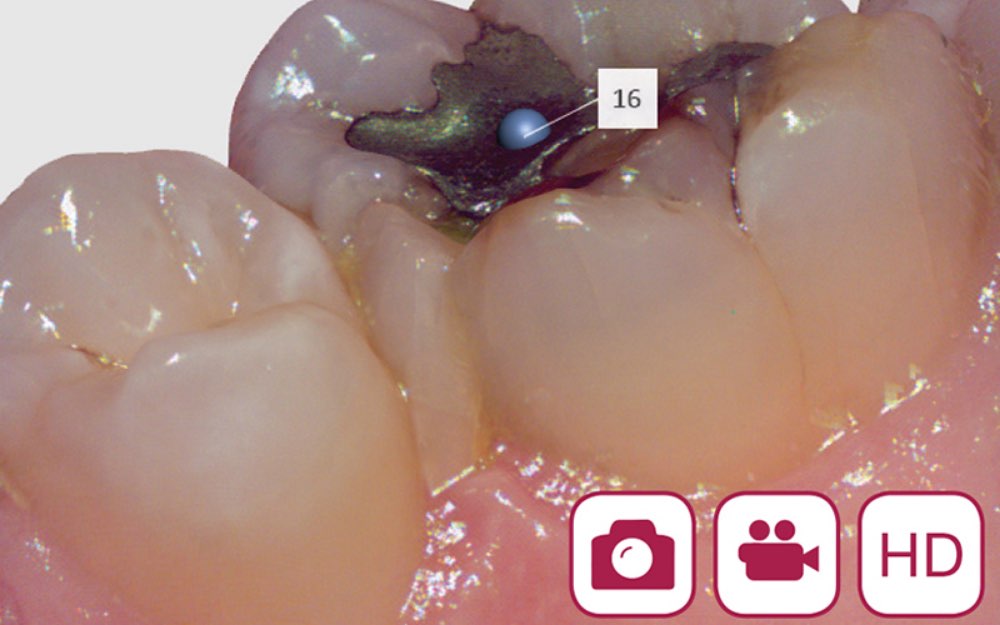

4|動画と静止画による精密なデータ取得

高精細な画像や動画を撮影できるカメラが搭載されているため、小さなむし歯なども見逃さずに記録することができます。そのため、歯型をとる以外にも矯正などさまざまなシーンで使用します。